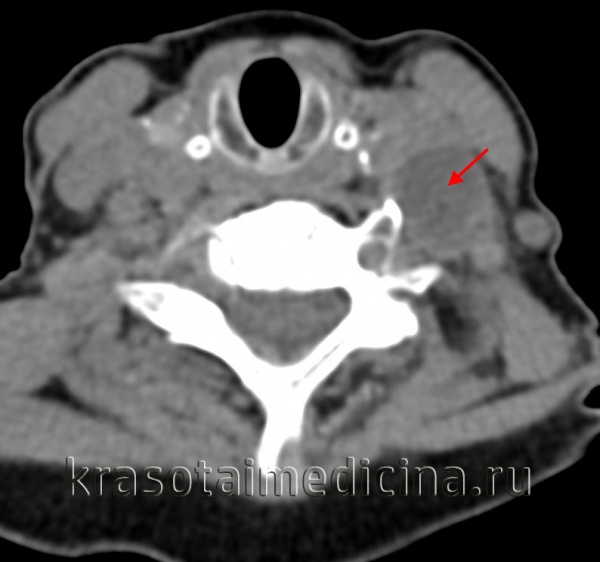

КТ шеи. Слева от средней линии в сонном пространстве кистозное образование (кистозно измененный лимфоузел).